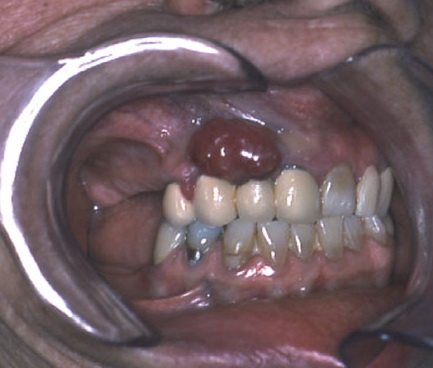

Oral mucosal melanoma= ميلانوم الاغشية المخاطية في الفم